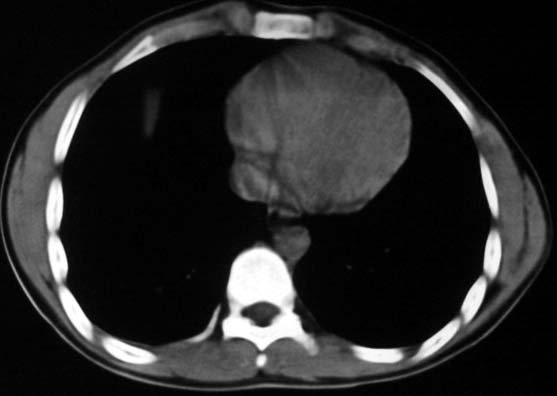

标题: CT5614:外伤病人男,20岁,右上腹痛.余肺野(-) [打印本页]

标题: CT5614:外伤病人男,20岁,右上腹痛.余肺野(-)

外伤病人男,20岁,右上腹痛,ct显示:右肺下叶后基地段见斑片状高密度影,密度不均,边界清,考虑1,右肺下叶肺挫伤;2,炎症。

可以肯定的是与外伤无关。肺挫伤是片状渗出影:边缘比中心密度低,呈毛玻璃状,如果是结节状肺挫伤(肺内血肿)应该边缘光滑,不会与后壁胸膜有轻度粘连。此病灶分叶状,周围有卫星灶(纤维条索影及小结结影),考虑结核.